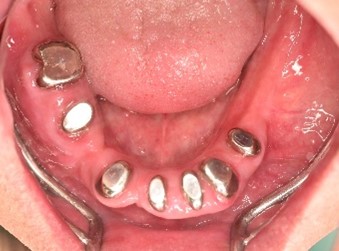

男性Iさん 50代(マグネット式入れ歯)

主訴

グラグラしている歯がある。歯並びをきれいにし、しっかり噛めるようになりたい。

治療内容

歯周病が進行し深刻な状態でした。保存することができない歯が上4本、下3本ありましたので、抜歯し、残った歯上4本、下7本の歯周病治療を徹底的にし、それらの歯を活用し上下マグネット式総入れ歯を入れました。

所感

治療前は、歯周病が進行し、重度に動揺している歯が4本あり、満足に食事ができない状況でした。マグネット式総入れ歯を装着後は、「なんでも思い通り噛むことができるだけでなく、歯並びもきれいになり、とても幸せです。」と、とても喜んでくださいました。

Before

赤丸は抜歯しました。上4本、下3本

After

【義歯を装着したところ】

【義歯を外したところ】

【マグネット式総入れ歯】

上顎

下顎